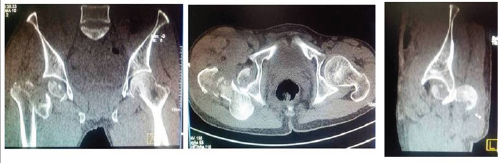

A 52 year old migratory laborer had an accident at civil construction site where he fell down from a height of 20 feet landing first on knees (in kneeling position). He presented to emergency department with severe pain in right groin, and inability to move the left lower limb. On examination the limb was shortened, externally rotated and a bony mass felt in the loin which did not move with the movement of distal thigh. There was severe tingling and decreased sensation in front and lateral aspect of leg and patient was unable to dorsiflex his ankle and toes. His pulsations were normal but he had had transient hypotension with tachycardia which corrected with initial resuscitation. First X ray showed fracture about right hip (Figure 1) mostly a trochanteric fracture but a careful evaluation showed incongruity of head and a "vacant" on super lateral acetabulum. A CT scan was followed wherein the fracture was better delineated. A posterior dislocation of hip with fracture about the trochanter was seen. The head was also fractured and the infra foveal part could be seen lying the acetabulum. A fracture line also ran through the posterior wall of acetabulum which was not more than 25% of the wall and also was undisplaced (Figure 2a- 2c). The patient was admitted and limb placed in Thomas splint and prepared for next morning. No attempts to reduce the dislocation were made.

Figure 2(a).